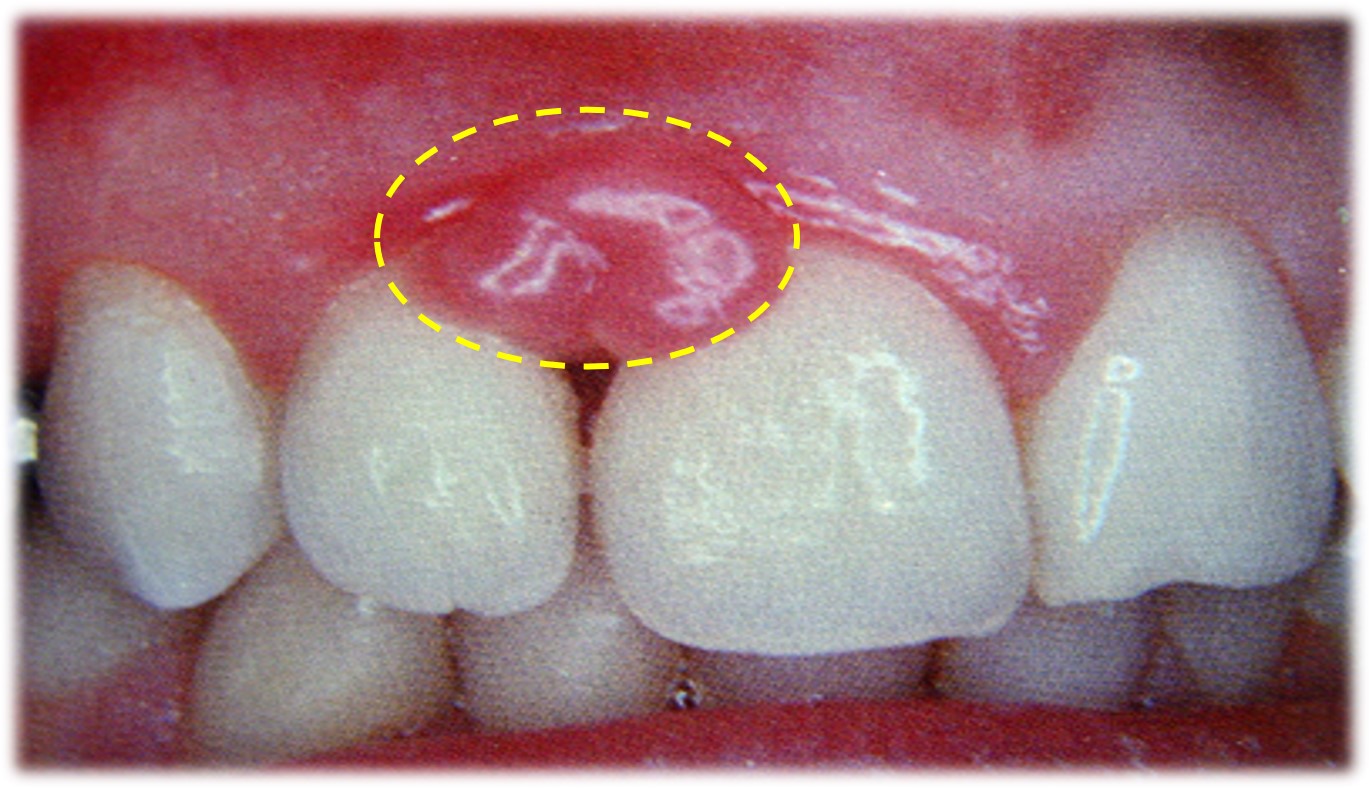

(二)血管性龈瘤

又称化脓性肉芽肿或妊娠性牙龈瘤,其病因与妊娠有关。

肉眼观:质软、紫红色包块(图16.1-3),常伴有溃疡和出血。

图16.1-3 血管性龈瘤(肉眼)